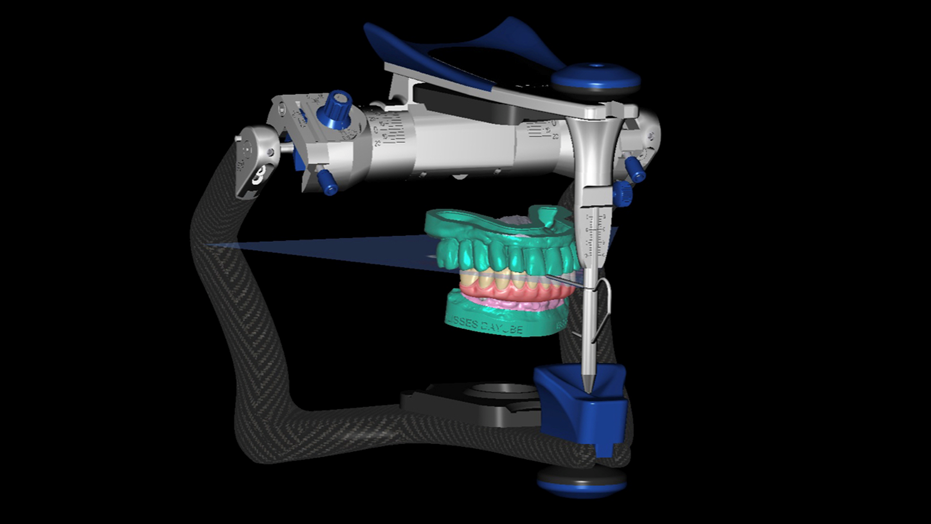

Ainda podemos montar os arquivos digitais no articulador virtual para ajustes necessários (Figura 9).